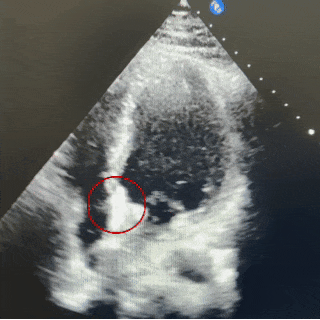

五腔心切面

封堵器锁定成型后,超声下多切面确认封堵器盘面贴合,稳定夹持缺损。